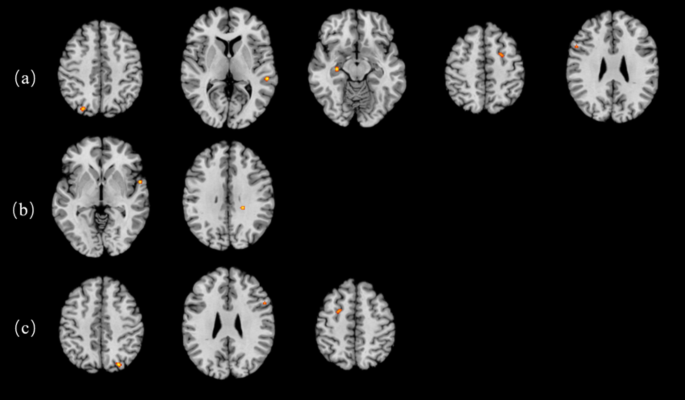

A total of 91 foci from 11 experiments were included by analyzing the coordinate points of brain regions activated by exercise-affected inhibitor function.(Table 2)21,22,23,24,25,26,27,28,29 which showed a total of five peak activation points, as shown in Fig. 2a; Table 2. Specifically, these peak activation points were located in the left superior temporal gyrus, left middle frontal gyrus, right inferior frontal gyrus, right precuneus and right parahippocampal gyrus.

Activation clusters for inhibition ALE analysis in standard MNI space. (a) Inhibition. (b) Incongruent. (c) Incongruent-congruent.

Further subgroup analysis was performed for the incongruent task minus the congruent task, and the results are shown in Table 5; Fig. 3.

Subgroup analysis according to age

In the children and adolescents group, the analysis included 8 foci derived from 2 publications23,29. The findings indicated that two peaks emerged during the performance of inhibitory tasks, with these peaks located in the caudate tail of the left cerebral sub-lobar region and the caudate body of the right cerebral sub-lobar region. In the adult group, a single study was incorporated, and the original article reported that brain regions exhibiting activation during the task were located in the right precentral gyrus and the left superior frontal gyrus. Within the older adult group, data from 68 foci across 5 studies21,24,26,27,28 were examined. The results revealed two peaks, one in the right precuneus and one in the right inferior frontal gyrus.

Subgroup analysis according to exercise type

In the aerobic exercise group, a total of 21 foci from four publications21,23,28,29 were included, and the results revealed that after the aerobic exercise intervention, a total of 1 activation peak was located in the left precuneus lobe. In the integrated exercise group, 58 foci from 4 publications21,24,25,26 were included. The results revealed that after integrated exercise, a total of 3 activation peaks occurred, which were located in the right precuneus, left middle frontal gyrus, and right inferior frontal gyrus.

Subgroup analysis according to exercise duration

In the acute exercise group, 19 foci from 3 publications25,28,29 were included, which showed a total of one peak activation point after acute exercise intervention, located in the left precuneus. In the chronic exercise group, a total of 60 foci from 5 publications21,23,24,27 were included, which showed a total of two peak activation points after chronic exercise intervention, located in the left precuneus and the right inferior frontal gyrus.

Activation clusters for inhibition ALE analysis in standard MNI space. (a) Children. (b) Older adult. (c) Acute exercise. (d) Chronic exercise. (e) Aerobic exercise. (f) Integrated exercise.